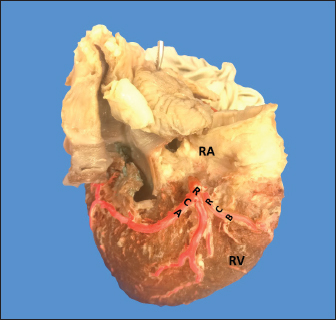

The average weight of the 28 bovine hearts used in our study was 1,534.1 kg. The RCA presented calibers of 5 ± 0.9 mm for the proximal third, 3.4 +/− 0.8 mm in the middle third and 2.3 ± 0.6 mm in the lower third (Fig. 1). The first segment of this artery presented an average of three arterial branches and the second segment had four branches. The RCA ended between the right margin and the crux cordis in 15 cases (53.6%), in 10 specimens (39.3%) it ended in the crux cordis, and in 7.1% in the middle third of the right atrioventricular sulcus (Fig. 2a).

Fig. 1. Anterosuperior view of the heart. (RA): Right atrium; (RV): Right ventricle; (RCA): Right coronary artery; (RCB): Right conus branch.